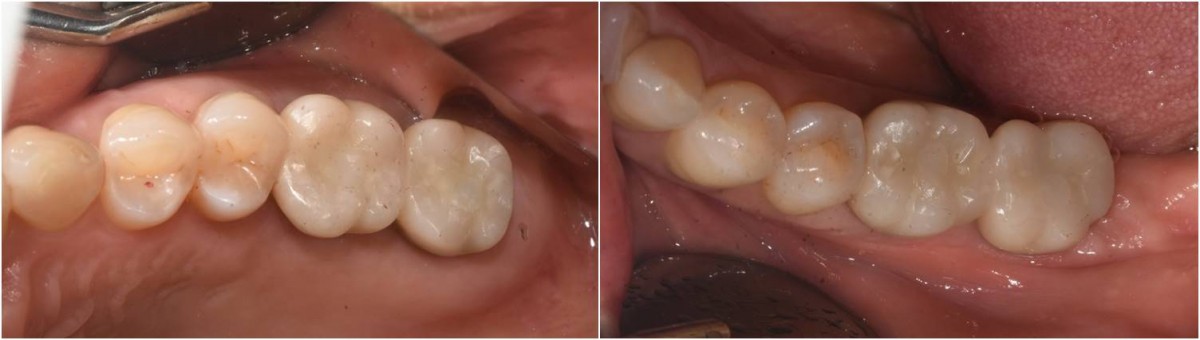

▲Panoramic radiograph after 1 year of the crown delivery.